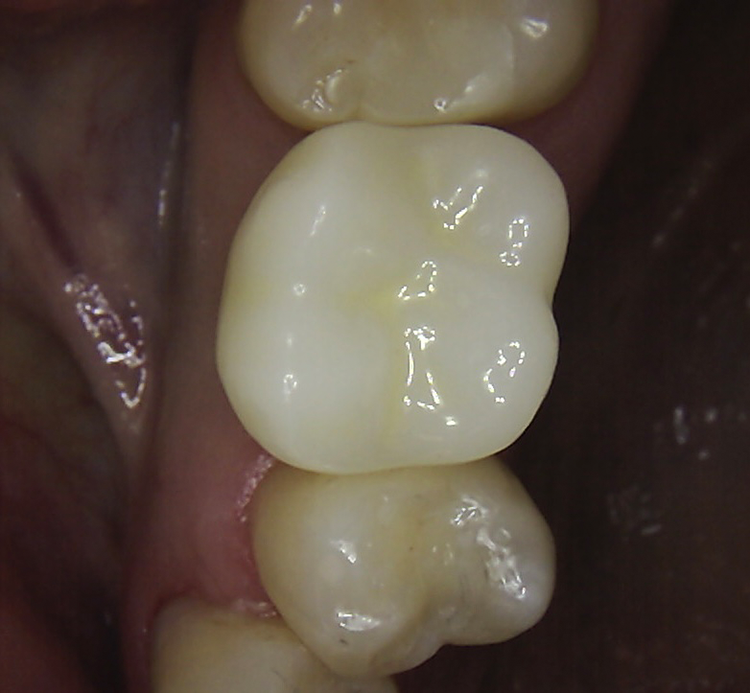

Abb. 2: Repräsentativer Fall von ABH Grad B Septus Typ II. a) Ansichten vor der Installation. Röntgenaufnahme der periapikalen Läsion an einem wurzelkanalbehandelten Molaren und klinische Ansicht der Typ-II-Socket nach der Extraktion. b) Die Ansichten nach der Installation zeigen das Implantat innerhalb des interradikulären Septums und das über dem Implantat platzierte A-PRF. c) Nachuntersuchungen nach 10 Tagen bzw. 2,1 Monaten. Die Röntgenaufnahme zeigt die Knochenbildung zwischen der Sinusmembran und dem apikalen Teil des Implantats. d) Jüngste Nachuntersuchung nach Einsetzen der Prothese.

Abb. 3: Repräsentativer Fall von Grad A Typ I. a) Präoperative Ansicht. Röntgenbild der periapikalen Läsion an einem wurzelkanalbehandelten Molaren. Die Höhe des Alveolarknochens zeigt Grad A an. b) Klinische und radiographische Ansicht der Implantatinsertion unter Verwendung einer Einheilscheibe mit großem Durchmesser (6×8 mm). A-PRF wurde um das Implantat und unter der Scheibe platziert. c) Nachuntersuchung nach 5,9 Monaten vor und nach der Zementierung und Aufbereitung. d) Jüngste Nachuntersuchung nach Einsetzen der Prothese

Die SDS-Zirkoniumdioxidimplantate wurden mit zementierten Pfosten weiter aufbereitet (Abb. 1d, 3 und 4c) und nach 4,74 + 0,95 Monaten Einheilzeit mit endgültigen Kronen versorgt. Die Balkonform ermöglichte ein natürliches Emergenzprofil, das die definitiven Kronen wie die Standardform ausrichtete sowie die Gesundheit des Weichgewebes und die Osseointegration förderte. Bei jeder Nachuntersuchung wurden Stabilität des Implantats, Zustand des umgebenden Gewebes und Vorhandensein von Zahnstein beurteilt.